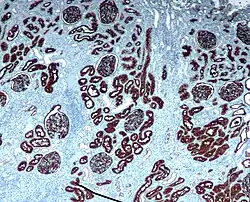

CD10 is used in clinical pathology for diagnostic purpose.

In epithelial tumors

- Clear cell renal cell carcinoma (Clear cell RCC)

- CD10+ distinguishes renal cell carcinoma, conventional type with eosinophilic morphology from its mimickers. Chromophobe carcinoma and oncocytoma are CD10−.[29]